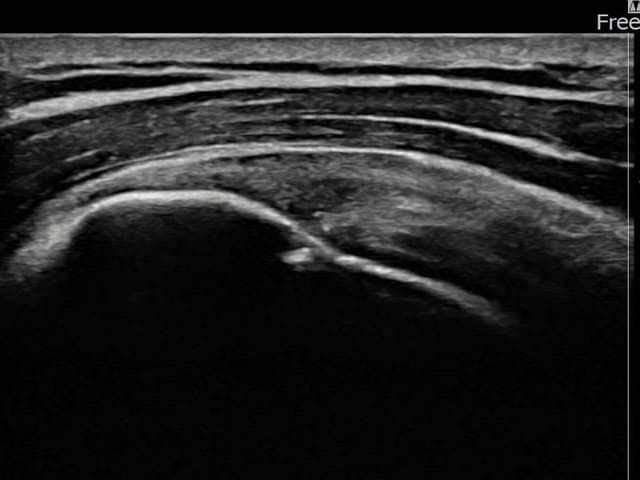

[촬영시기:22.09.05~22.12.08]

[어깨인대 축소봉합술] 우측 어깨 통증과 팔 들어 올리기 제한으로 내원하셨습니다.